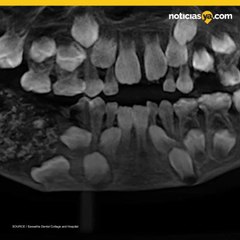

¿En qué momento debo empezar la limpieza de los dientes en mi niño?